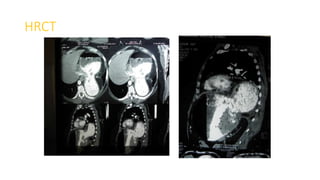

HRCT

Diagnosis

Left sided Bochdalek hernia with stomach herniating into left chest.

PLAN

Laparoscopic repair of Bochdalek hernia with reinforcement by dual mesh.

• Misdiagnosis of BH is common, as reported in this case, and may be

• CT Scan are the only way to direct visualize the focal defect of

diaphragm, and also helps in establishes a definitive diagnosis

Conclusion

• BHs are uncommon clinical findings in adult population and cases

presenting with incarceration are even less common

• CT is preferred diagnostic tool for BHs

• Laparoscopic repair of an incarcerated BH is an excellent option

because of the advantages of its unique, minimally invasive nature